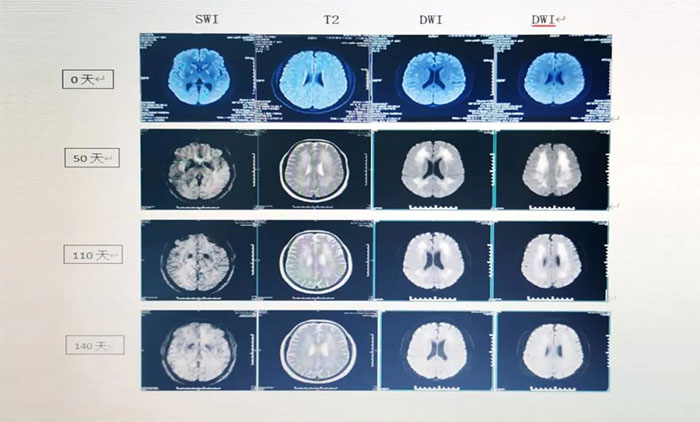

▲ ANE影像学:具有多灶性、对称性脑损害的特点,病变内出血和环形强化为经典影像学表现。ADC加权像上呈特征性“同心圆结构”。

▲ 患者影像变化

经过会诊,张静波主任团队制定了完善的治疗方案,给予靶向药物托珠单抗及地塞米松治疗,同时予继续对症及支持治疗,以及高压氧、经颅磁刺激等治疗。经上述治疗两个月后,患者病情明显好转,神志清晰,行走自如,可以正常与人交流,大小便也恢复正常,目前已经康复出院。